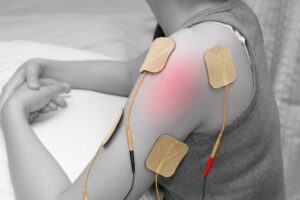

استفاده از تجهیزات پیشرفته فیزیوتراپی

تجهیزات مدرن نقش مهمی در تسریع روند درمان دارند. دستگاههای الکتروتراپی، لیزر درمانی و تمرین درمانی پیشرفته میتوانند التهاب را کاهش داده و عملکرد عضلات را بهبود بخشند.

کلینیک فیزیوتراپی خانه سلامت با بهرهگیری از مجهزترین تجهیزات، خدمات فیزیوتراپی زانو را با بالاترین استاندارد ارائه میدهد.